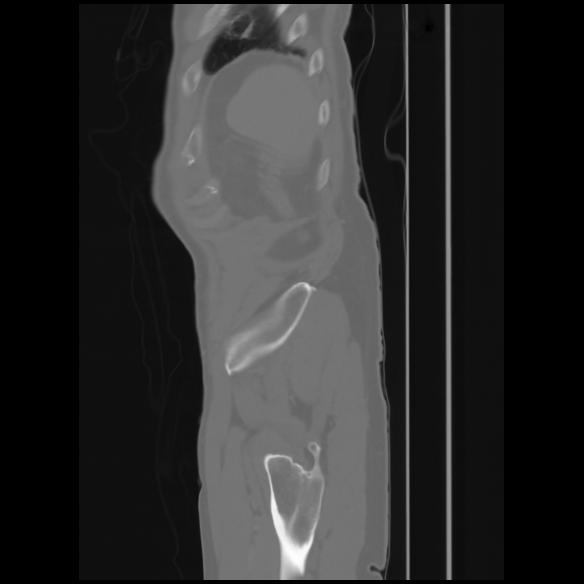

7 CUERPO,CE,Sagittal,3.000,CUERPO,Sagittal,